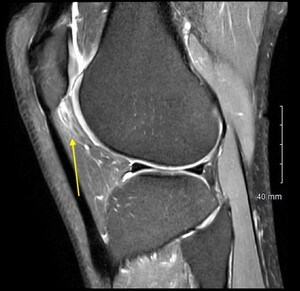

On exam she had pain to palpation of the anterolateral fat pat, with mild patellofemoral crepitus. Her range of motion was 0-130 degrees. Ligamentous exam was stable with full strength in quadriceps and hamstrings on manual muscle testing. Magnetic Resonance Imaging (MRI) demonstrated subtle thinning of the lateral patellar articular cartilage, fibrosis of the infrapatellar fat pad, and distension of the infrapatellar bursa (Figure 1). Otherwise, her MRI was unremarkable.